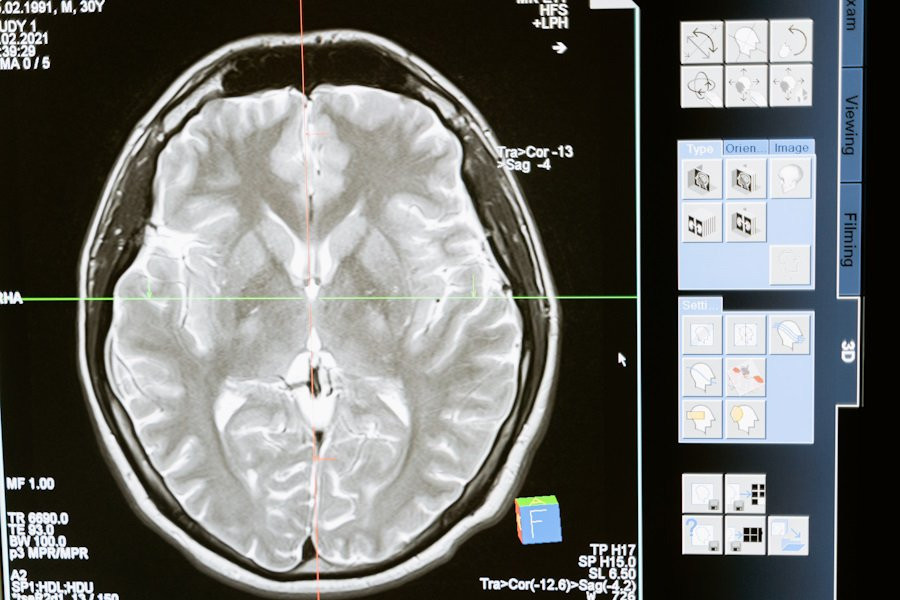

Изыскания, проведенные учеными LMU Munich (Германия), раскрыли ключевые механизмы регенерации нервных клеток мозга, что может пролить свет на новые методы лечения неврологических заболеваний. Исследование, опубликованное на портале Nature Neuroscience, сосредоточилось на прямом нейрональном перепрограммировании, процессе, позволяющем преобразовывать локальные глиальные клетки в функциональные нейроны.